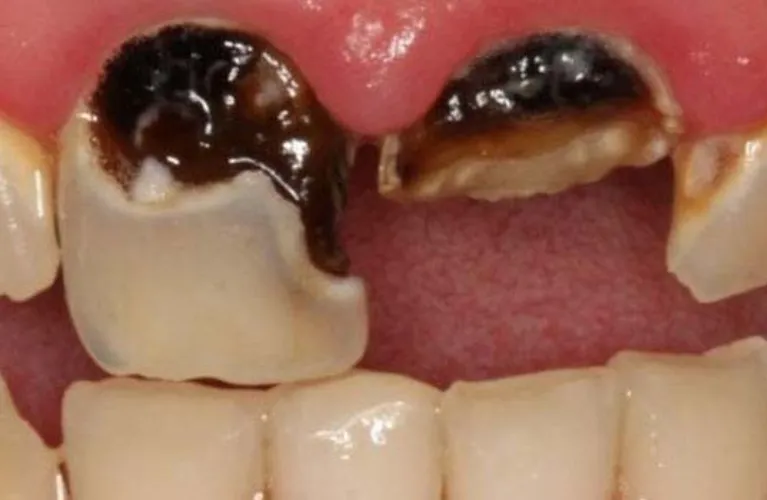

Impacted wisdom teeth

Wisdom teeth, also known as third molars, often don’t have enough space to emerge properly, leading to pain, infection, and potential damage to nearby teeth. In such cases, extraction is recommended.